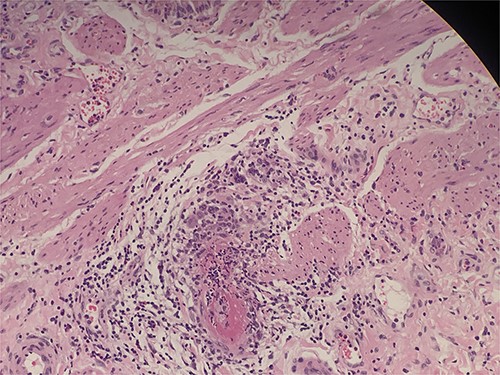

He underwent laparoscopic cholecystectomy under general anesthesia in the standard way. The gallbladder was found to be macroscopically inflamed with few omental adhesions. The procedure was completed peacefully, and the patient recovered well. The histology of the gallbladder specimen came back showing features of necrotizing vasculitis of small and medium arteries suggestive of PAN (Figs 1–3). He was treated with steroids for his systemic vasculitis and has shown significant improvement in his symptoms. His kidney function also markedly improved.

Intraluminal thrombi, fibrinoid necrosis with perivascular infiltration by lymphocytes, neutrophils, and eosinophils (H&E 200X).